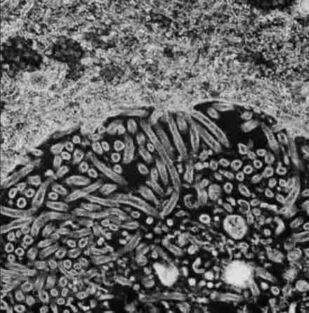

Патология служит своеобразным мостом, объединяющим базовые науки с клинической медициной, и выступает в качестве одной из научных основ для более глубокого понимания болезней. Современная патология активно использует в своем арсенале последние достижения клеточной и молекулярной биологии для всестороннего изучения структурных, биохимических и функциональных изменений клеток, тканей и органов, лежащих в основе различных заболеваний.

Выявленные патологом изменения находят свое отражение в нарушениях на глубинном уровне функционирования клеток, внеклеточного матрикса, субклеточных структур, на уровне повреждения тканей, и в итоге формируют симптомы и синдромы у пациента. Так понимание причин, механизмов, морфологических и биохимических связей при повреждении клетки ведет к пониманию клинических проявлений заболеваний и подходов к их лечению.